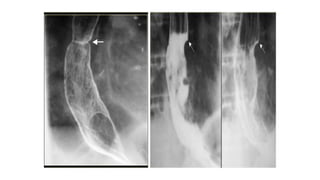

• A 4 cm segmental narrowing with an irregular margin and shouldering

appearance at the distal half of the esophagus suggests tumoral

infiltration.

• Evidence of prior sternotomy is noted.

Gastric cardia cancer invading the distal esophagus

(barium swallow)

• Severe stricture with shouldering appearance is present at the distal

portion of the esophagus and gastric cardia that causes pre-stricture

dilatation and contrast media stasis compatible with esophageal

pseudoachalasia.

• A 4cm segmental narrowing with an irregular margin and shouldering appearance at the distal half of the esophagus suggests tumoral infiltration. • Evidence of prior sternotomy is noted.

Gastric cardia cancerinvading the distal esophagus (barium swallow) • Severe stricture with shouldering appearance is present at the distal portion of the esophagus and gastric cardia that causes pre-stricture dilatation and contrast media stasis compatible with esophageal pseudoachalasia.